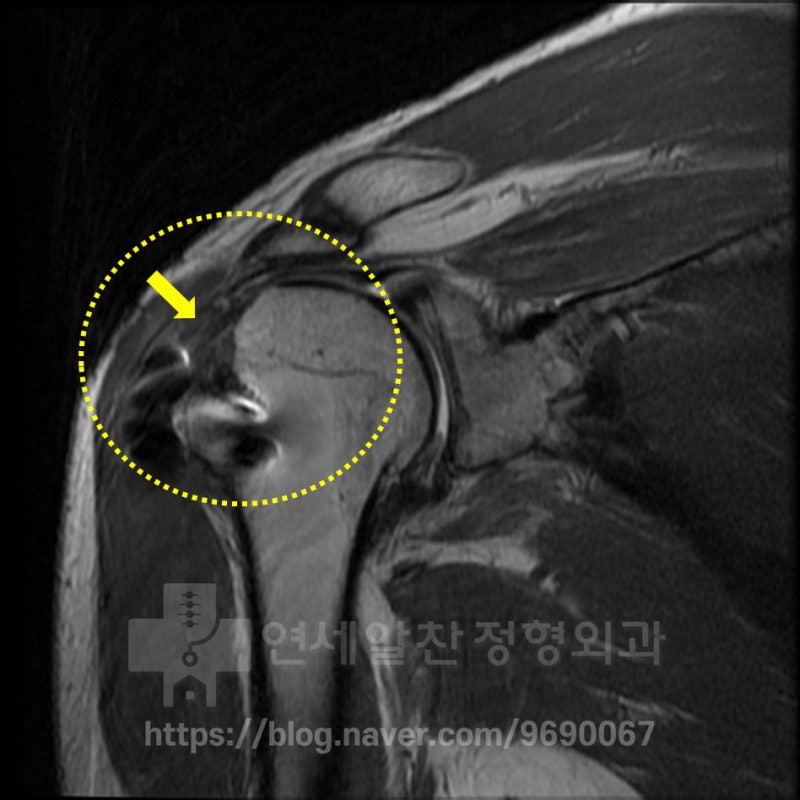

MRI 상에서도 상완골 대결절의 뼈의 소실이 심하게 관찰되며 극상근의 인대가 아주 얇은 종이처럼 약화되고 파열된 것이 관찰됩니다. 이러한 상태에서 재수술은 매우 꺼려지는 상황입니다. 나이가 젊은데 인대는 아주 좋지 않고 상완골의 뼈의 소실이 심해서 아무리 수술을 잘한다고 하더라도 이전만큼의 활동력이나 결과를 예측하기 어렵기 때문입니다. 이러한 상황이다 보니 어느 의사도 재수술을 하겠다고 하기가 어려운 상태였습니다. 환자는 어렵게 저에게 내원하게 되었고 재수술을 결정하였습니다.

극상근의 긴장도가 아주 좋게 관찰되며 검은 색으로 보이는 부분(노란색 화살표)이 인조인대로 보강을 한 것인데 불규칙한 상완골의 대결절을 완벽하게 덮고 있으며 원래의 극상근과도 잘 치유된 것이 관찰됩니다. 무엇보다도 환자가 수술전 느꼈던 통증을 현재를 느끼지 않고 매우 행복해 한다는 것입니다. 근력강화, 기능부전에 대한 회복은 꾸준한 재활을 통해 점진적으로 좋아질 것이라 생각됩니다 . 이번 케이스로 느끼는 것은 처음 전문의의 진단이 잘못될 경우 환자에게 좋지 않은 치료 결과를 가져온다는 것입니다. 이번 환자분처럼 전문의의 잘못된 진단으로 인해 불필요한 수술을 받을 경우 제대로된 치료를 받지 못하고 치료 시기를 놓쳐 병원을 다니면서도 병을 키우게 되기 때문입니다.